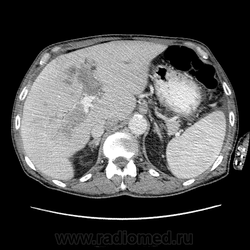

Здравствуйте, коллеги! Мужчина около 70 лет. Жалобы: слабость, утомляемость около 3х месяцев, чувство тяжести на желудке после еды. Анамнез: онко не было. С вышеописанными жалобами обратился ко врачу, сделали ФГЭДС - признаки гастродуоденита, по биопсии - N. В течение 2х последних недель существенно похудел и начал желтеть. Выполнена МСКТ

А как насчет холангиокарциномы с тромбозом воротной вены и мтс в средостение, лимфоузлы брюшной полости и забрюшинного пр-ва?

Внимательно пересмотрел, признаков характерных для ГЦР не нашел (кроме тромбоза). Согласен с холангиокарциномой, ещё бы отсроченную фазу, для печени минут через 12-15 .

1. Гиперденсивность, в артериальную фазу  всей опухолевой массы (опухоль хорошо васкуляризирована)

2. Гиподенсивность, в портальную фазу (быстрое вымивание, опять же обусловлено васкуляризацией)

3.Тромбоз портальной вены.

Для холангиокарциномы характерно гиперденсивность, в отсроченную фазу, за счет аффинитета к контрастному веществу.